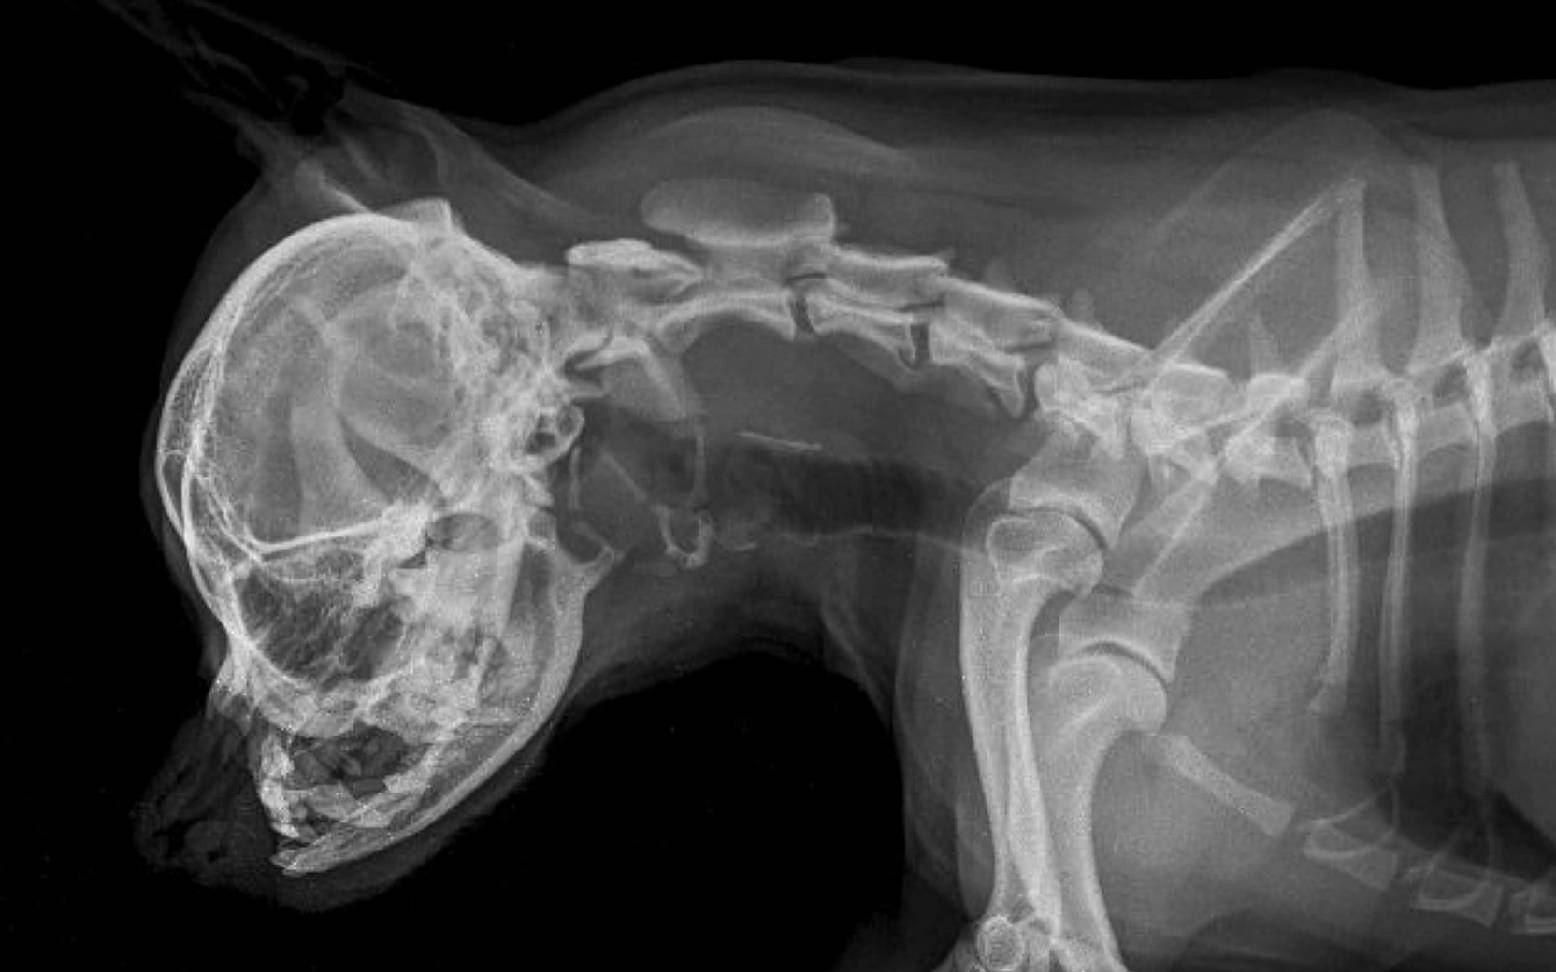

The word brachycephaly comes from Greek and means short-headed or round-headed. It describes the hereditary shorter and wider skull shape of some dog and cat breeds, which is reminiscent of the "childhood pattern" of young animals. The health consequences of this shortened facial skull are far-reaching and are referred to as brachycephalic syndrome.

Brachycephalic syndrome is caused by centuries of selective breeding to inhibit the growth of the facial skull. In relation to the smaller facial skull, the size of the tissues inside has not decreased during development. This leads to narrowing, malformations, and thickening in the nose and larynx. Since dogs, like cats, are obligate nasal breathers (=they must breathe through their nose), this explains why these changes cause such a wide range of problems for these animals. Breeds affected include French and English bulldogs, Pugs, Boston terriers, Cavalier King Charles spaniels, Pekingese, Lhasa Apsos, Pinschers, and Persian cats.

The nostrils of affected animals are too narrow and the nasal conchae in the nose are too large for the small skull. The animals have to exert significantly more effort when inhaling in order to overcome this resistance in the airways. This creates negative pressure in the larynx and trachea, which can lead to further narrowing or even collapse of these structures (see article on tracheal collapse). The consequences are sniffling, snoring, grunting, or wheezing noises that can be heard with every breath. These additional breathing noises are neither normal nor typical of the breed and do not reflect well-being, as is often mistakenly assumed by owners.

Additional breathing difficulties, including severe respiratory distress, can result from a palate that is too long, thickened, or flaccid. During inhalation, this palate covers the opening of the larynx, partially or completely closing it. Furthermore, a shortened pharynx, a relatively large tongue, laryngeal collapse, which is particularly common in pugs due to unstable laryngeal cartilage, or excessively developed mucosal folds can lead to worsening breathing difficulties.

After a thorough general examination and your detailed preliminary report, your veterinarian will often be able to make a preliminary diagnosis. The throat and larynx will then be examined more closely. As this can almost only be done under sedation or anesthesia, this examination is usually combined with surgery. Further X-ray or CT scans can be used to determine the exact extent of the changes.